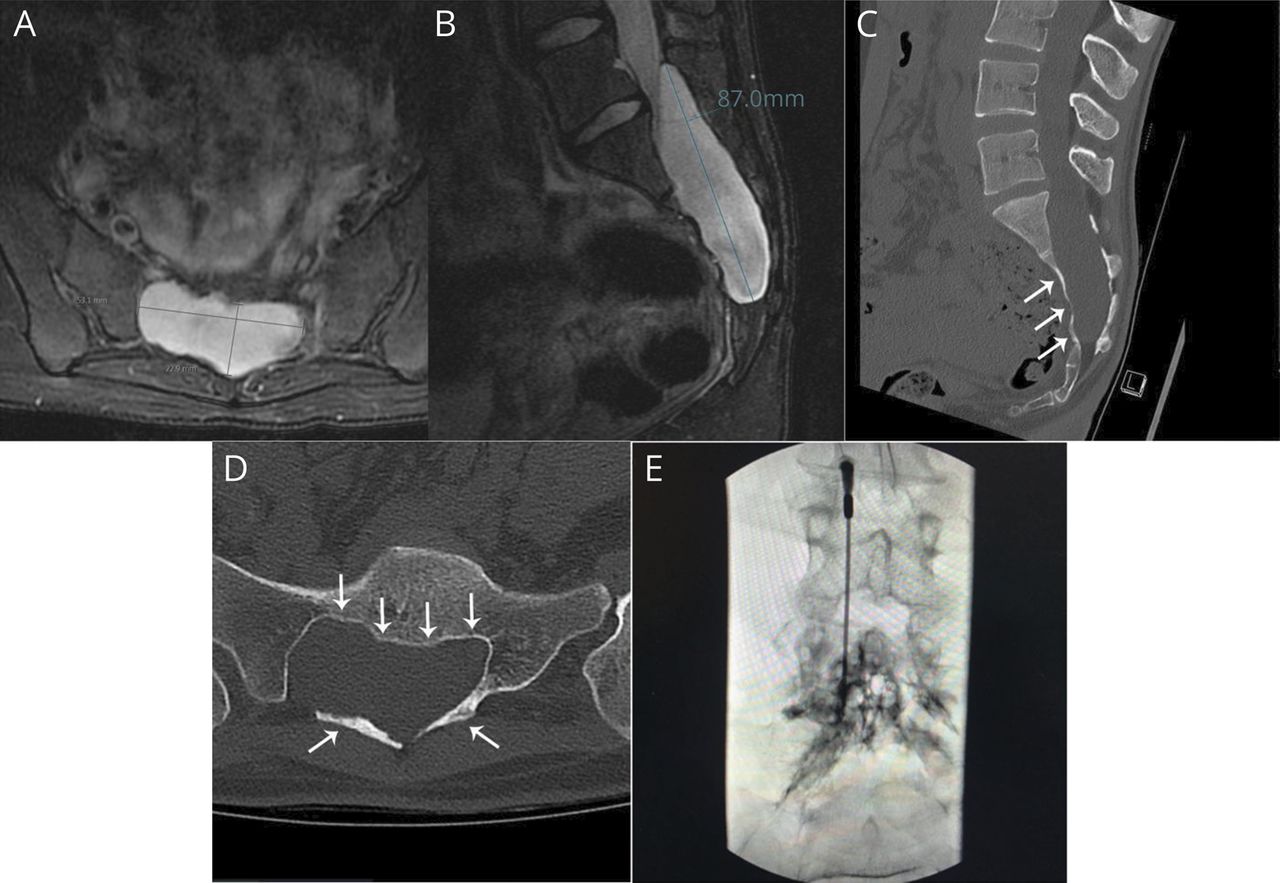

一位19岁的妇女5年历史的头痛诊所日常头痛和腰痛坠马后,降落在她的臀部。她的病史是不起眼的。她被诊断出患有偏头痛和非特异性的肌肉骨骼背部疼痛。布洛芬没有提供救济。她不能上学是因为她的症状。她的神经系统检查的。核磁共振的头,没有钆最初解释为正常。的全脊柱MRI和没有钆演示了一个大(85.1毫米×23.4毫米×52.9毫米)nonenhancing包含fluid-intensity病变在骶管空间(从mid-L5 S4段)(图中,A和B)报道Tarlov或蛛网膜囊肿。没有硬脑膜的扩张。脊柱CT扇形边和扭曲的骶骨与骨重建一致(图中,C和D)。不需要进行腰椎穿刺或CT脊髓x光像。后来透露,她在历史上产生了深远的直立性头痛(更糟的是正直的)组件。

基于clinical-radiologic相关性,脑脊液漏患者被怀疑和有针对性的硬膜外血补丁(30毫升)的网站fluid-intensity病变(图E),立即改善症状。然而,症状慢慢回到武器基线在未来2年,一个探索性行手术。暖暖的少量硬膜撕裂和沟通缺陷(之间的大型fluid-intensity病变和蛛网膜下腔)被证实在S1水平在手术。诊断为脊髓硬膜外的蛛网膜囊肿。肌肉移植和纤维蛋白胶(3毫升)被用来密封的硬脑膜的缺陷加上部分排水囊肿。她决议完整的症状在1年随访,回到全日制学校。后续磁共振脊柱分辨率下降是由于症状。

许多脊柱怀疑脑脊液压力低的表现可以看出如脑膜憩室,extrathecal CSF集合,脊髓空洞症,retrospinal c1流体集合。金宝搏188手机app1在我们的例子中,影像学特点及骶管fluid-intensity病变的位置很容易被误解Tarlov囊肿,这是最初报道了核磁共振成像。Tarlov囊肿是一种CSF-filled在骶神经根囊肿最常见的发现水平和Tarlov囊肿的确切原因尚不清楚。有一种理论到神经根鞘出现脑脊液漏创伤性损伤后通过先天性异常连接之间的蛛网膜下腔和影响周围神经(围神经的地区)。3Tarlov囊肿可以成为症状和成长由于流体从集结点较resistentiae导致压缩相邻结构如神经根。它很少可以脑脊液漏的原因是否破裂到硬膜外的空间。3脊髓硬膜外的蛛网膜囊肿可引起的一种罕见的硬脑膜的小缺陷,导致脑脊液积累和缺陷收集和蛛网膜下腔之间的沟通。4这类似于脑膜憩室的胸椎由于突出的蛛网膜通过自发的硬脑膜的眼泪,它可以与脑脊液漏。1,4

很难区分这两种类型的囊肿或确定位置(硬膜内的或硬膜外的)仅通过核磁共振。CT或磁共振(MR)脊髓x光像可以提供更多的信息。在我们的例子中,一个硬脑膜的缺陷在手术过程中被确认。这是造成脑脊液漏,在骶管形成一个集合。集合的大小是实质性的和骨重建了(图中,C和D),这可能占我们的病人的背部疼痛。这一发现具有治疗意义为骶集合或囊肿症状有时通过排水管理。金宝搏188手机app在我们的例子中,这可能导致恶化的症状进一步降低脑脊液压力和复发的液体收集在一个未经处理的硬脑膜的缺陷。3,5